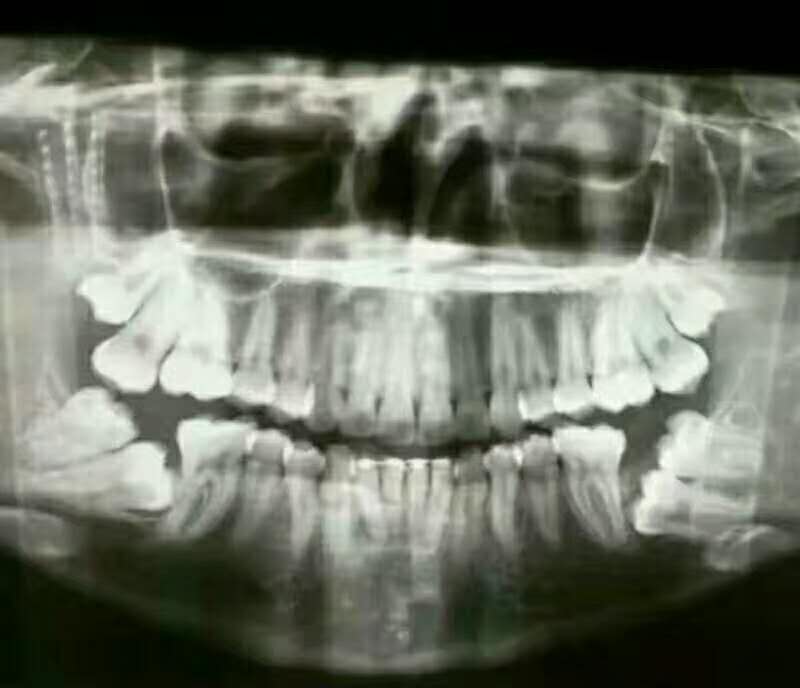

牙病,是发病率灰常高的一种常见病。患牙病后是应当保守治疗?还是应将病牙连根拔掉?这是个令人迷惑的问题。

一般情况下,大多数病牙可以通过补牙、镶牙、牙周病治疗等方法进行挽回,只有一部分病牙,因病变发展到无法治疗的地步,不得不提前“退休”。

阻生牙

阻生牙是经常遇见的情况,尤其是智齿,极易出现阻生牙的情况。

阻生牙会导致邻牙的牙根吸收、蛀牙、牙周炎、牙列拥挤和冠周炎等,给口腔的健康造成极为不利的影响,因此需要尽早进行拔除。